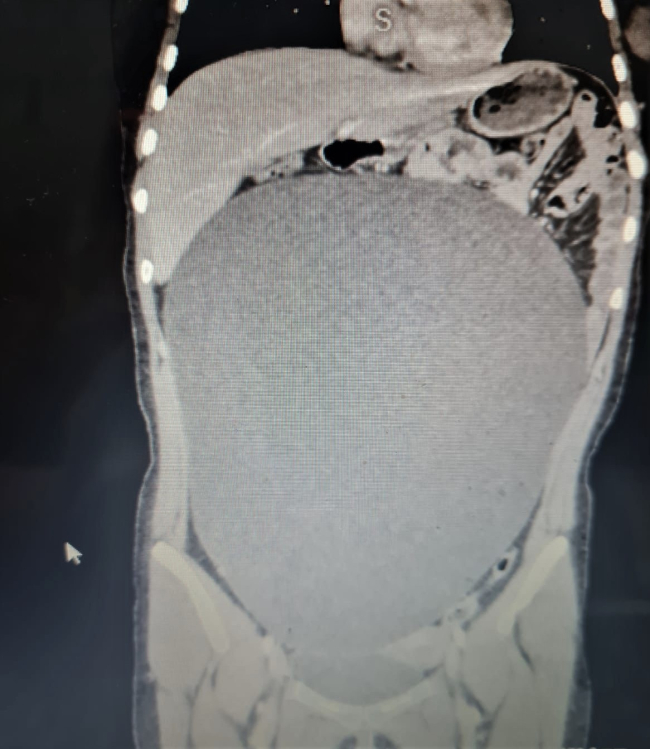

Aksaray’da geçirdiği kaza sonucu hafif yaralanan B.G hastaneye kaldırıldı. Tedavi esnasında karnında 8 kilogram kitle tespit edilen B.G ameliyatla sağlığına kavuştu.

Lise öğrencisi B.G'ye (17), 25 Ağustos'ta Ankara Caddesi'nde halk otobüsü çarptı. Kaza nedeniyle vücudunun çeşitli yerlerinde kırıkları olan B.G, Aksaray Eğitim ve Araştırma Hastanesine kaldırıldı.

Burada yapılan tetkiklerde genç kızın karın bölgesinde anormal biçimde büyümüş bir kitle olduğu tespit edildi.

Hastanenin Çocuk Cerrahi Bölümü Uzmanı Dr. Öğretim Üyesi Ayşe Betül Öztürk tarafından acil şekilde ameliyat edilen B.G'nin karnından 60 santimetre çapına ulaşan yaklaşık 8 kilogramlık kitle başarıyla çıkarıldı.

Serviste hastanın tedavisine başladıklarını, tomografisinde karnında oldukça büyük bir kitle olduğunu gördüklerini anlatan Öztürk:

"Neredeyse bu kitle tüm karnını kaplıyordu. Aileyle görüşerek hızlı şekilde ameliyat kararı aldık. Ameliyat çok başarılı geçti. Sağ yumurtalık kaynaklı kitle başarılı şekilde alındı. Kitlenin organları sağa ve sola doğru sıkıştırdığını gördük. Kitle akciğer zarıyla temas halindeydi. Alt taraftan idrar torbasından akciğer zarına kadar uzanan oldukça büyük bir kitleydi. Bu kitle çok büyümüştü, eğer öğrenilmeseydi patlayabilirdi. Bu durumda da hayati tehlike ortaya çıkabilirdi. Daha da büyüyebilir ve ameliyat edilemez bir duruma gelebilirdi"